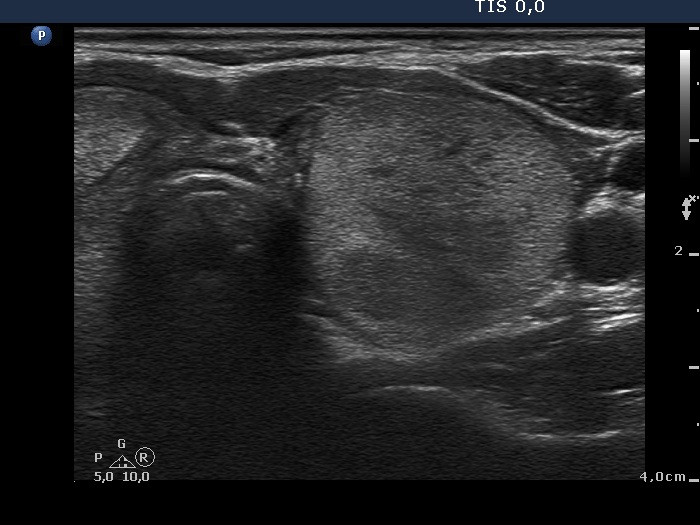

Ethanol sclerotherapy: non-toxic solid nodules - Case 5

Twelve years after the therapy (ultrasonographic picture 6)

Middle part of the left lobe, horizontal scan. This is the lower, larger part of the previously treated nodule.